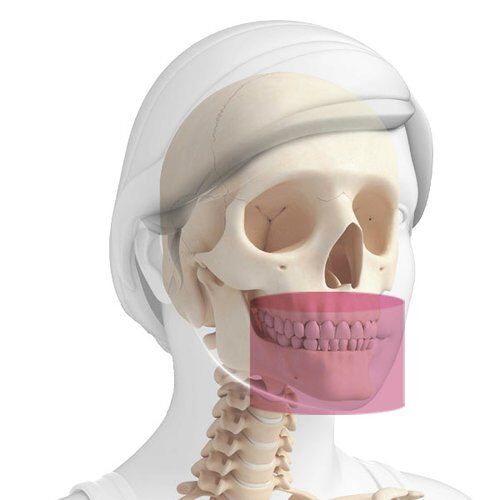

Spécialisations pour lesquelles il est possible d'utiliser le diagnostic 3D.

EXAMENS OTO-RHINO-LARYNGOLOGIQUES

Oreille : 7 x 6 cm (XF)

Nez et sinus maxillaires : 13 x 8 cm

Bouche et gorge : 13 x 10 cm

Ensemble des voies aériennes supérieures : 13 x 16 cm

EXAMENS ODONTOLOGIQUES

AVANCÉS

Dentition jusqu’aux frontaux : 13 x 16 cm

Rami ascendants mandibulaires : 13 x 10 cm

Zygomas et sinus : 13 x 8 cm

Sinus maxillaires : 10 x 10 cm

Éléments dentaires : 4 x 4 cm (XF)

DE BASE

Dentition complète adulte : 10 x 8 cm

Une seule arcade complète adulte : 10 x 6 cm

Dentition complète enfant : 8 x 8 cm

Une seule arcade complète enfant : 8 x 6 cm

Hémi-arcade ou dentition frontale : 6 x 6 cm

EXAMENS ORTHOPÉDIQUES

Articulation Temporo-Mandibulaire : 7 x 6 cm (XF) bouche ouverte/bouche fermée

Rachis cervical : 9 x 9 cm (XF) - Voxel 68 μm